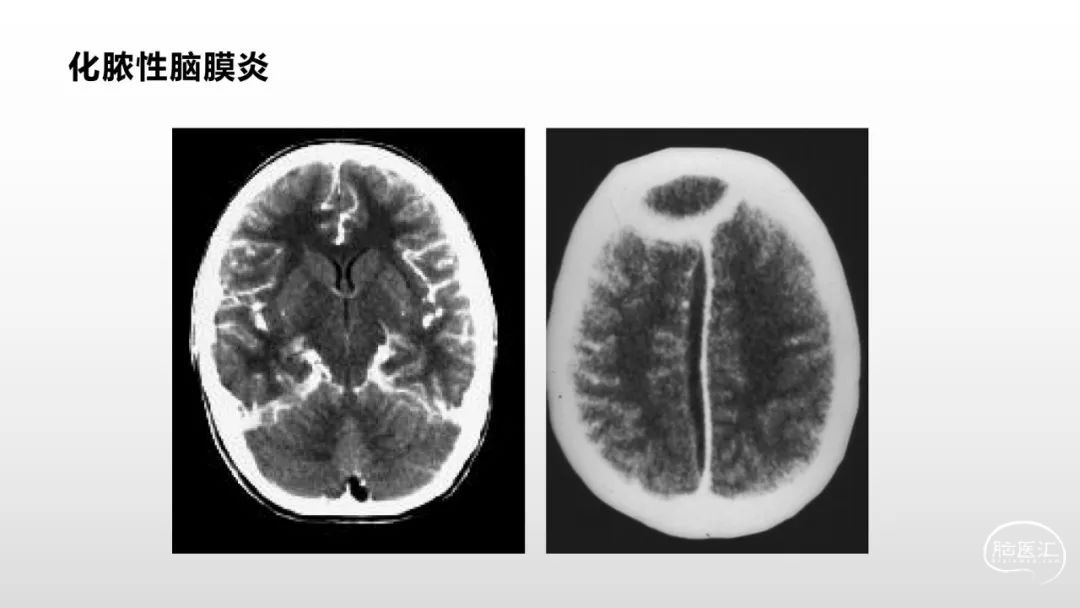

颅脑影像诊断基础知识讲座:脑膜病变